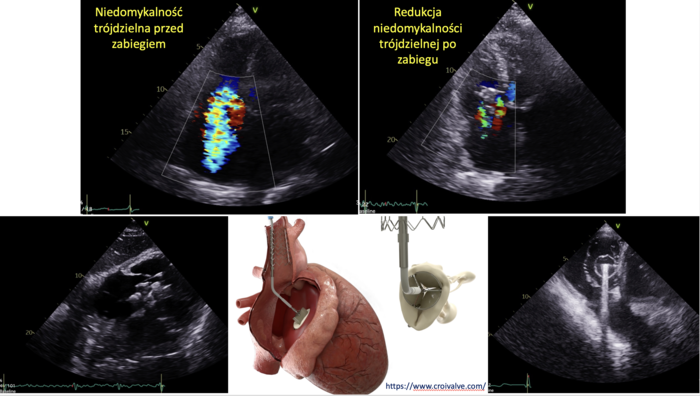

W Uniwersyteckim Centrum Klinicznym, szpitalu klinicznym GUMed przeprowadzono 5 na świecie zabieg wszczepienia choremu systemu CroíValve DUO Tricuspid Coaptation Valve. Pacjentka z niedomykalnością zastawki trójdzielnej serca, która wcześniej nie była w stanie wykonać najprostszych czynności, dziś może funkcjonować samodzielnie.

– Jedyną opcją był CroiValve – nowatorski zabieg, który został przeprowadzony dopiero u kilku chorych na świecie. Jest to system, który współpracuje z zastawką trójdzielną serca pacjenta. W jej wnętrzu umieszcza się mniejszą biologiczną zastawkę, uszczelniającą strukturę od środka, natomiast od zewnątrz jest ona zabezpieczona przez płatki będące elementem pierwotnej zastawki pacjenta. Dodatkowo system mocowany jest poza sercem na stencie umieszczonym w żyle głównej górnej. CroíValve DUO Tricuspid Coaptation Valve wprowadza się przezcewnikowo, w niewielki sposób ingerując w strukturę serca – tłumaczy dr hab. Dariusz Jagielak z Katedry i Kliniki Kardiochirurgii i Chirurgii Naczyniowej GUMed.